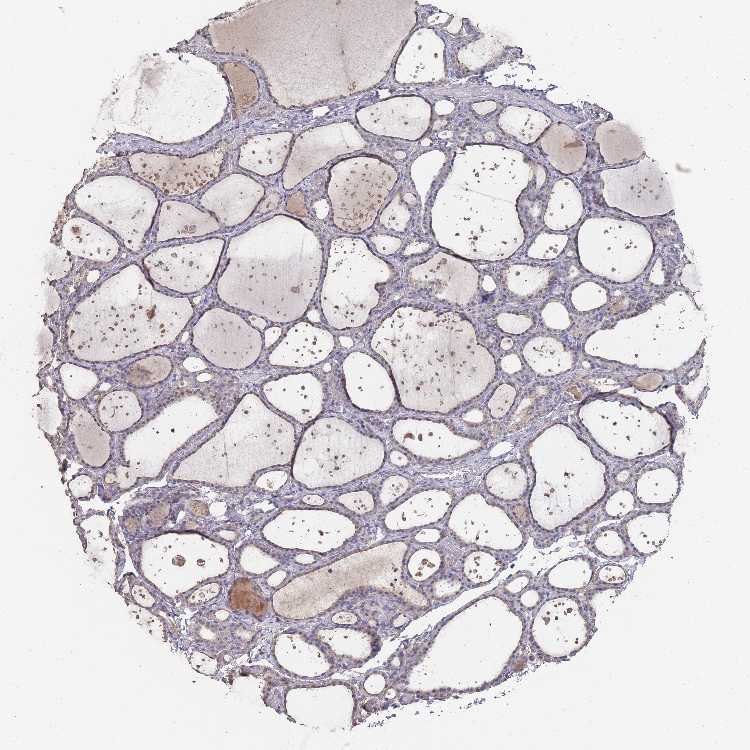

THYROID GLAND - Antibody stainingi

Antibody staining in the annotated cell types in the current human tissue is reported as not detected, low, medium, or high, based on conventional immunohistochemistry profiling in selected tissues. This score is based on the combination of the staining intensity and fraction of stained cells.

Each image is clickable and will lead to virtual microscopy that enables deeper exploration of all samples and also displays staining intensity scores, fraction scores and subcellular localization as well as patient and tissue information for each sample.

Antibody HPA049325

Glandular cells Low